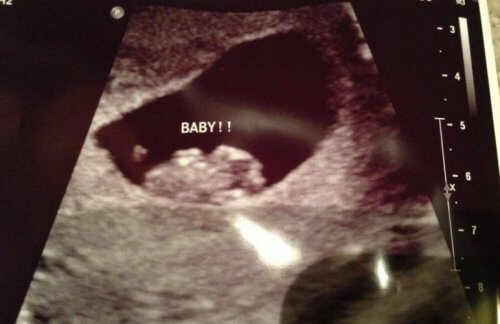

Vous êtes enceinte et vous êtes curieuse de connaitre le sexe de votre bébé ? Soyez tranquille, car il est possible d’obtenir cette information dès la première échographie.

Comment arriver à un tel taux de réussite ? Il faut simplement être attentif à l’emplacement du placenta lors de la première échographie que réalise la femme au début de sa grossesse.

Bien que les membres commencent à se développer à partir de la 4eme semaine de grossesse la méthode Ramzi permet de connaitre le sexe du bébé grâce à l’étude des images avant la 8eme semaine de grossesse.

Certains parents se trompent au moment de prédire le sexe du bébé car ils essayent de se fier à la position du bébé. Cependant, vous ne devez pas vous focaliser sur la position que le bébé occupe mais plutôt que la position du placenta lui-même. Au début, les bébés se positionnent au centre du placenta mais le plus important est de chercher la partie brillante qui l’entoure.